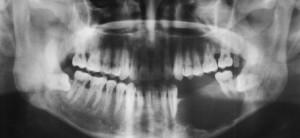

Остеогенную саркому челюсти практически невозможно диагностировать на начальных стадиях. Для постановки точного диагноза врач назначает следующие виды обследований:

- рентгенологическое исследование;